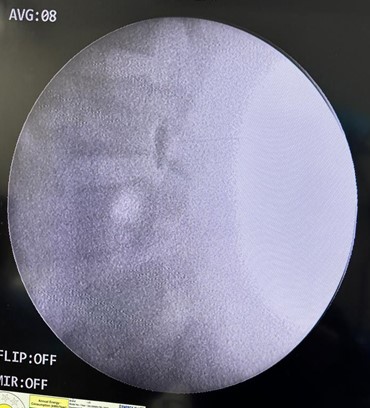

- Technique: Facet joint pain is carried by medial branches of dorsal rami of spinal nerves or simply the medial branch. This technique damages this nerve, thereby treating the pain. A specialised instrument called radio frequency ablation is used that when set at desired frequency and amplitude produces heat to damage the medial branch.

- Technique: Genicular nerves namely superior medial nerve, superior lateral nerve and inferior medial nerve carries the pain of knee. They are ablated by radio frequency energies using an instrument called radio frequency ablation. The procedure is performed in local anaesthesia.